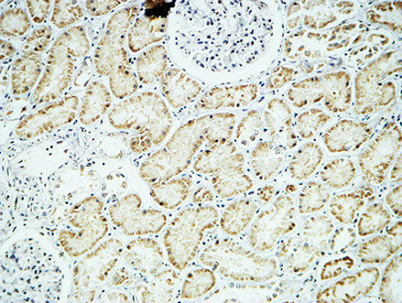

Product name: Crystallin-αB rabbit pAb

Dilutions: Western Blot: 1/500 - 1/2000. Immunohistochemistry: 1/100 - 1/300. ELISA: 1/5000. Not yet tested in other applications.